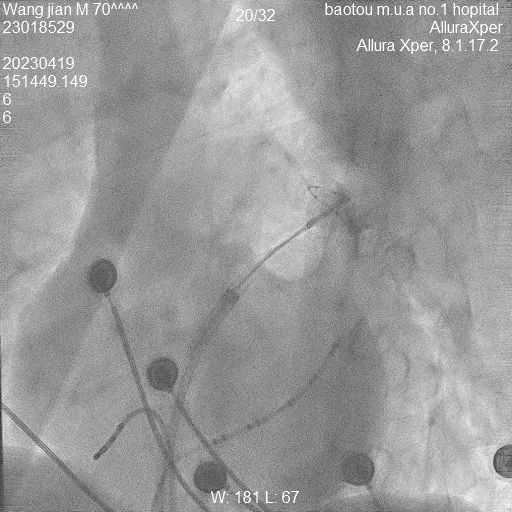

据了解,患者王先生今年70岁,房颤病史已经持续了1年,尽管一直以来坚持规律用药,但仍然觉得心悸、气短,活动耐量明显下降。10多年前王先生曾因“室上性心动过速”接受过传统的射频消融手术治疗,由于各种原因,王先生术中感觉不适,因此非常抵触这类治疗方式。针对该情况,包医一附院心内科三病区医护团队经过认真评估,判断王先生也同样适合“分段式肺静脉前庭冷冻消融”,该术式与传统射频消融术相比,患者体验明显舒适,术中几乎毫无痛感。此外,因该术式同时干预参与房颤形成的肺静脉前庭,扩大了消融部位,使得术后房颤复发的概率大大降低,极大提高了手术的成功率,是目前更为先进的冷冻消融术式。手术经过一小时顺利完成,王先生的心脏如期恢复了正常的窦性心律。

于此同时,手术时间也缩短许多,传统射频消融术耗时2至3小时,而AFA冷冻球囊消融术的手术时间约为60分钟,对于体质脆弱、心肺功能较低的老年患者,冷冻消融术更具有一定的时间优势,更快完成治疗过程。除此之外,传统射频消融术的高温会给患者带来烧灼疼痛感,部分患者术中需使用镇静剂来缓解疼痛。而AFA冷冻消融术通过液态制冷剂的吸热蒸发,带走组织热量,使得患者痛楚程度大大降低,在耐受性上会比射频消融术好。同时,AFA冷冻消融部位的表面组织相对平滑光整,血栓附着概率较低,且发生心肌穿孔、食道损伤等并发症的风险较低。可以完全避免传统射频消融术高温灼烧组织时间过长而导致的血栓、心包填塞、心房食管瘘等严重并发症。